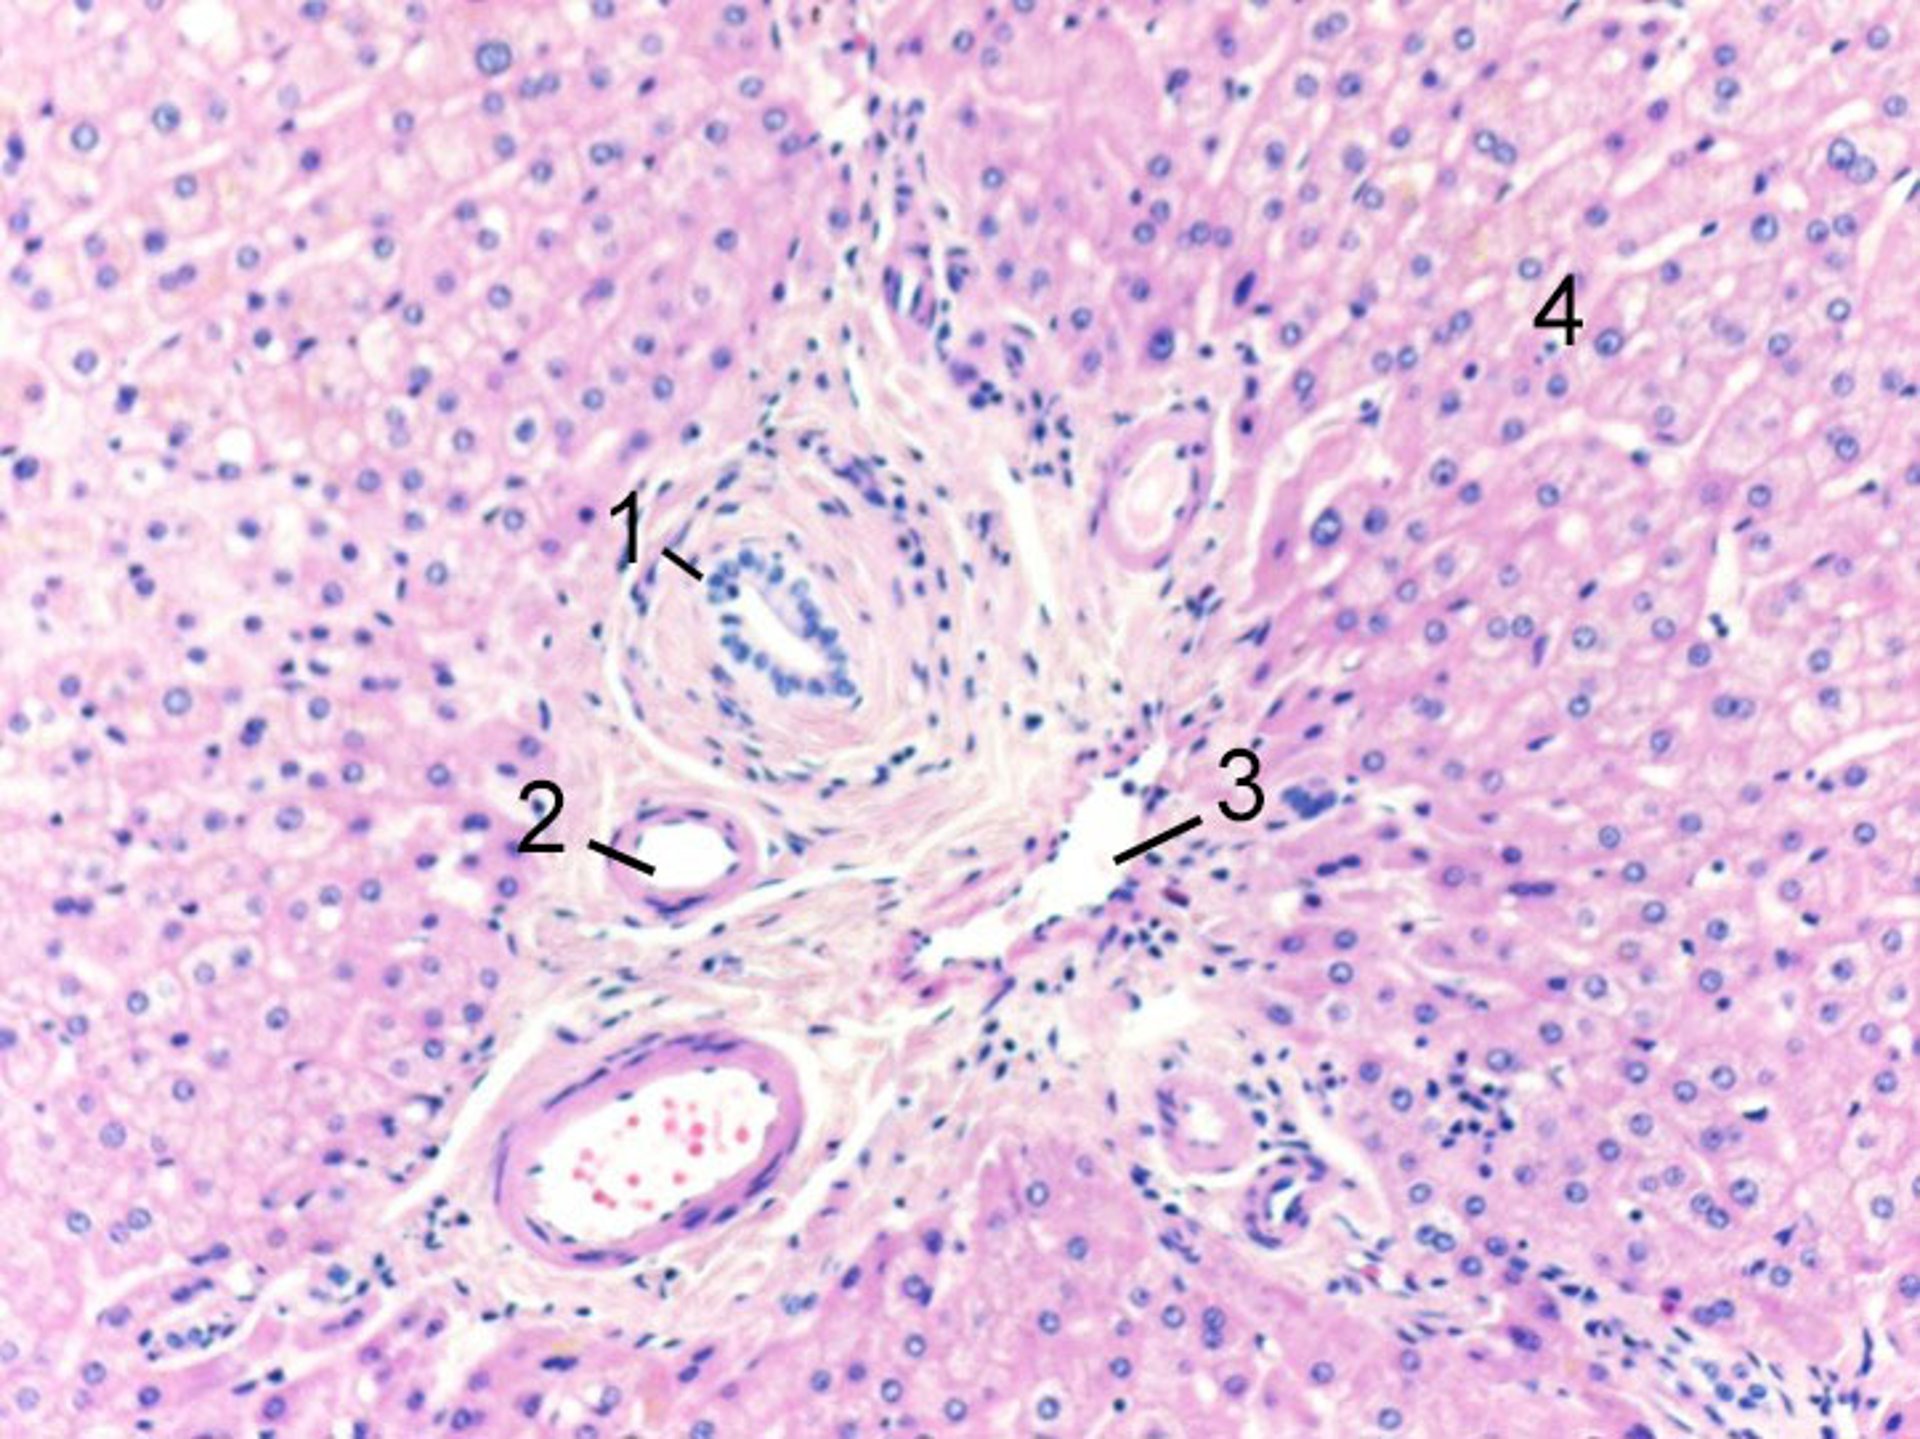

A nivel celular, los hepatocitos están organizados dentro de un lobulillo, que es un grupo de células de forma hexagonal con una vena hepática en el centro, y tríadas portales alrededor de la periferia. Las tríadas portales están compuestas por ramas terminales paralelas y adyacentes de conductos biliares, venas porta y arterias hepáticas. La sangre fluye desde la arteria hepática y la vena porta (en las tríadas portales) en la periferia, a través de los sinusoides entre los hepatocitos, hacia la vena central. En consecuencia, los hepatocitos en el centro del lobulillo son más susceptibles a la isquemia porque el oxígeno y los nutrientes fueron extraídos por los hepatocitos mientras la sangre fluía a través de los sinusoides desde la periferia. Canales más pequeños, llamados canalículos biliares, drenan la bilis secretada por los hepatocitos hacia los conductos biliares intrahepáticos en la periferia.

1 = Rama del conducto biliar; 2 = rama de la arteria hepática; 3 = rama de la vena porta; 4 = hepatocitos.

Image courtesy of Danielle Tholey, MD, and M. Isabel Fiel, MD, MS, FAASLD.